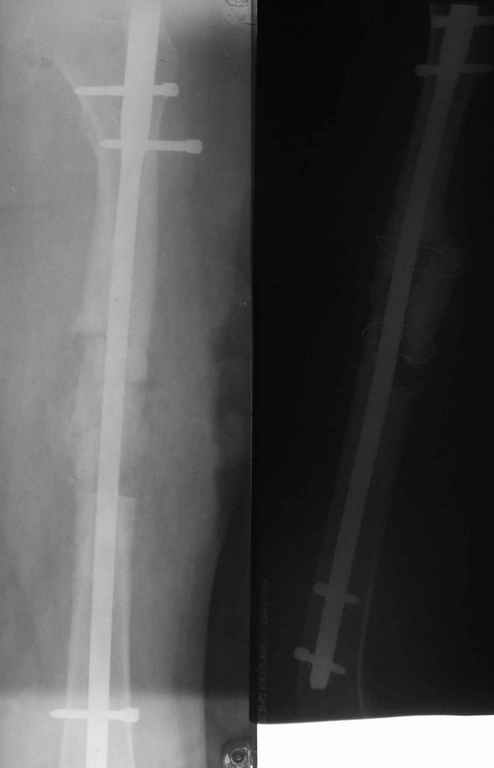

Здравствуйте коллеги. Сегодня поступил юноша 13 лет с повторным переломом правого бедра на стержне. Первый перелом был зимой 2003 году, синтезирован 2-мя стержнями Богданова. В июне 2003 года миграция стержней - стержни убраны. Повторный перелом в декабре 2003 года. Произведён МОС стержнем. Сегодня повторный перелом на стержне. Конечность уложена на шину Беллера. Господа, как можно удалить данный стержень? Чем предпочтительнее, на Ваш взгляд, синтезировать данный перелом у молодого растущего юноши с ожирением П ст.: пластиной, простым стержнем или стержнем с блокированием? ЭОПа у нас нет, поэтому пользуемся наборами ДЕОСТа с дистальной навигацией.

Снимок только при поступлении один.

Image(037)кор.jpg